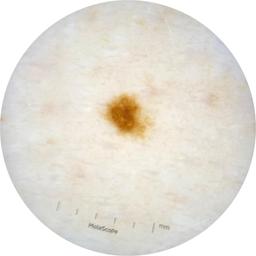

ISIC_2261268

2061 x 2061

Clinical

Field Value

acquisition_day 307

age_approx 50

anatom_site_1 Trunk

anatom_site_2 Posterior trunk

anatom_site_general posterior torso

concomitant_biopsy False

diagnosis_1 Benign

diagnosis_confirm_type single image expert consensus

family_hx_mm False

fitzpatrick_skin_type I

image_manipulation instrument only

image_type dermoscopic

lesion_id IL_8976478

patient_id IP_9156603

personal_hx_mm True

sex female